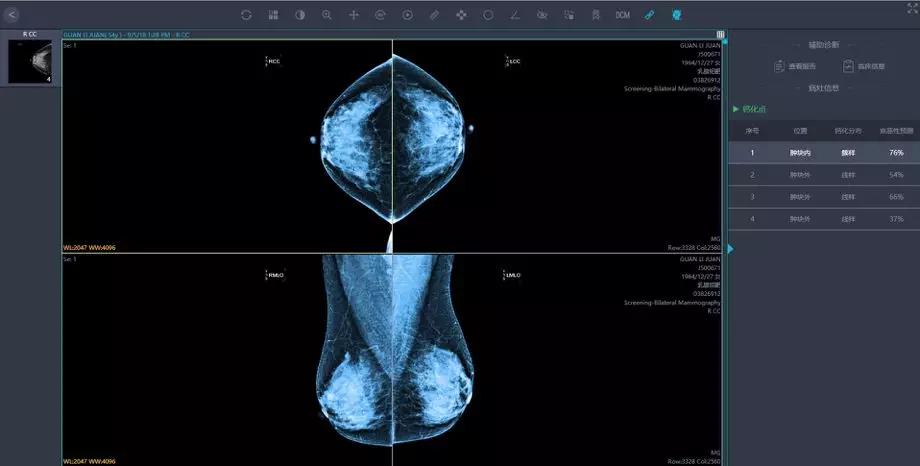

將這些影像學(xué)及臨床資料匯集,就為人工智能技術(shù)提供了大數(shù)據(jù)基礎(chǔ)。人工智能的影像識別和深度學(xué)習(xí)能力,能夠幫助醫(yī)生篩除正常影像,著重標(biāo)注疑似病灶的區(qū)域,讓影像科醫(yī)生審片更加精準(zhǔn)高效。

人工智能在影像識別的速度上勝于人工操作,同時也有利于臨床醫(yī)生制定針對性的治療方案, 特別對于偏遠地區(qū)和基層醫(yī)生而言,這一技術(shù)的應(yīng)用更加意義重大。

人工智能技術(shù)可以進行多模態(tài)影像數(shù)據(jù)融合,多維度,立體化進行數(shù)據(jù)融合分析,為乳腺癌的診斷及治療提供全面的個體化的綜合信息。

針對來自多個醫(yī)療中心的海量影像數(shù)據(jù),英特爾至強服務(wù)器提供最高達768GB的超大內(nèi)存,配合多核心多線程處理能力,對乳腺采集影像進行像素級別的特征識別,在紛紛擾擾的世界中尋找蛛絲馬跡,發(fā)現(xiàn)潛在問題。

匯醫(yī)慧影公司曾在胸部結(jié)節(jié),神經(jīng)系統(tǒng),甲狀腺等多器官系統(tǒng)影像與國內(nèi)外頂級醫(yī)院的影像及??漆t(yī)生進行過人機讀片對比,經(jīng)過深度學(xué)習(xí)的人工智能系統(tǒng),讀片準(zhǔn)確率達到90%。

英特爾至強服務(wù)器可將深度網(wǎng)絡(luò)模型優(yōu)化并將數(shù)據(jù)集進一步加強,也將會繼續(xù)幫助提高該識別準(zhǔn)確率,其對數(shù)據(jù)的分析和比較“眼力”,早已突破人類極限,達到醫(yī)療影像辨識的新高度。